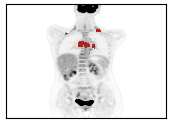

There has been growing research interest in using deep learning based method to achieve fully automated segmentation of lesion in Positron emission tomography computed tomography(PET CT) scans for the prognosis of various cancers. Recent advances in the medical image segmentation shows the nnUNET is feasible for diverse tasks. However, lesion segmentation in the PET images is not straightforward, because lesion and physiological uptake has similar distribution patterns. The Distinction of them requires extra structural information in the CT images. The present paper introduces a nnUNet based method for the lesion segmentation task. The proposed model is designed on the basis of the joint 2D and 3D nnUNET architecture to predict lesions across the whole body. It allows for automated segmentation of potential lesions. We evaluate the proposed method in the context of AutoPet Challenge, which measures the lesion segmentation performance in the metrics of dice score, false-positive volume and false-negative volume.